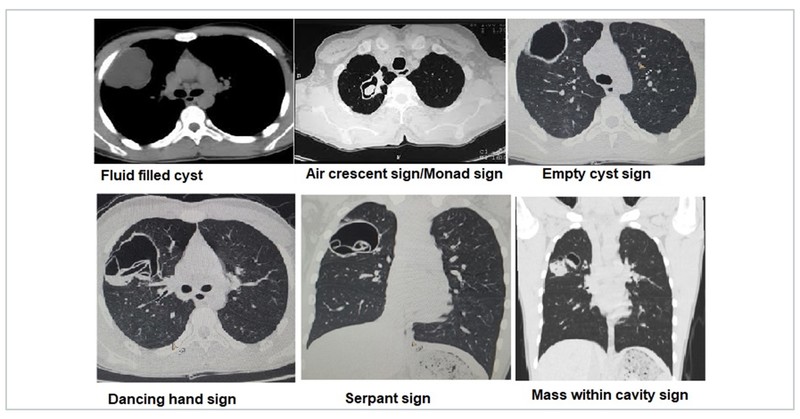

Hydatid cyst

Hydatid cyst has been associated with various CT signs. An unruptured hydatid cyst may appear as a fluid filled cyst. Post rupture or aspiration the hydatid cyst can appear as air crescent sign, water lily sign/Camalote sign, crumpled membrane sign/dancing hand sign, empty cyst sign, serpant sign, or mass within cavity sign.